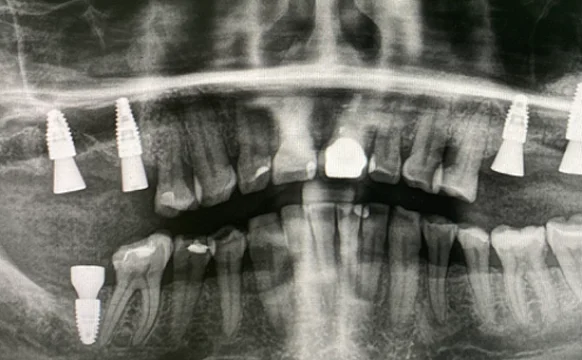

Установка имплантатов Straumann BLT

Проблема

подвижные зубы и отсутствие зубов

Врач

Мамедов Эльшан Мехманович